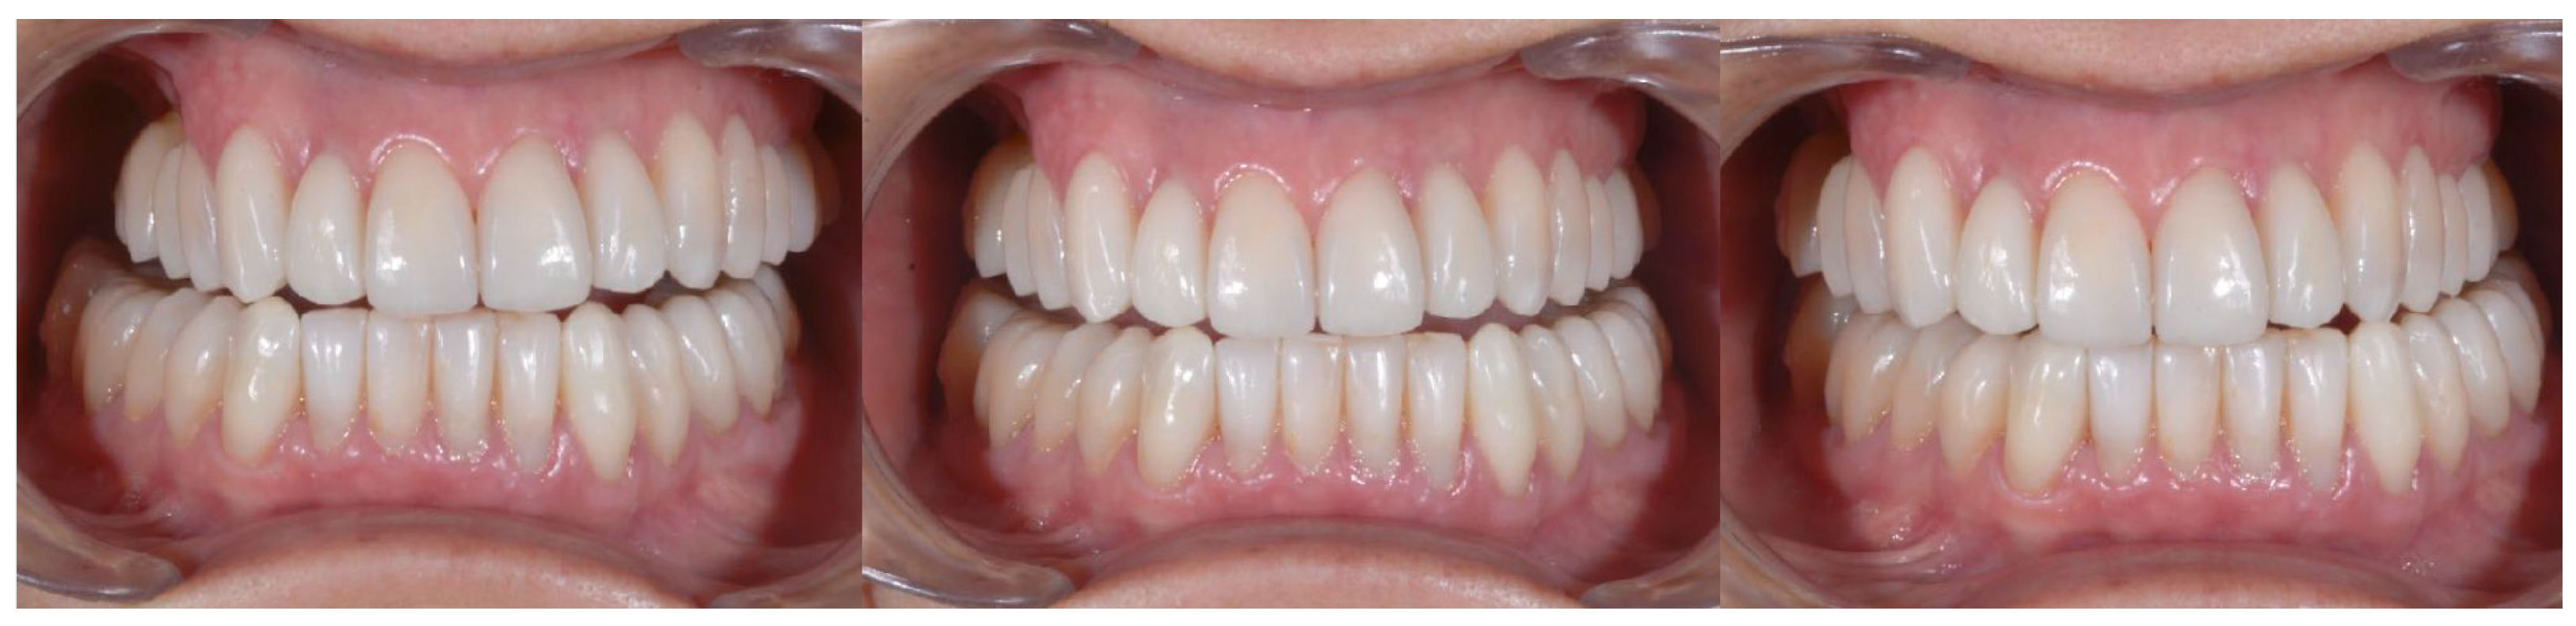

| Parameter Examined | Clinical Significance | Result Obtained |

|---|---|---|

| Smile symmetry | Smile symmetry refers to the mirror agreement between the two sides of the mouth but can also consider the bi-pupillary line, the incisal line, and the labial commissure. | YES |

| Horizontal symmetry | It originates from the presence of similar elements placed in a regular sequence, as verified in a dentition with teeth well aligned in the horizontal plane. | YES |

| Vertical symmetry | Recall the same principle as above, referring to the vertical direction. | YES |

| Repeated report | It indicates the division of space into portions that may not be identical in shape and size but arranged to generate a harmonious connection between them. This is what is verified between opposing hemiarches with well-arranged teeth, inspiring a sense of order and balance. | YES |

| Prospective effect | The contour of the buccal surface and the alignment of the inclined planes of the teeth is decisive in generating a correct perspective effect. The different length or strong color difference of even one element can impair the perspective effect and compromise the sense of harmony of the whole. | YES |

| Lip height | Useful distinction in static and dynamic harmony. The average height of the upper vermilion is 7.1 mm in the male and 7.7 mm in the female. The lower vermilion is normally more extensive, about 10 mm on average; these are statistical values, with wide individual variations. | YES |

| Lip line | The height of the upper lip, relative to the upper central incisors, can be classified as low, medium, or high, on the basis of the amount of crown exposure. | YES |

| Smile line | Smile line is a curved line passing through the incisal margin of the upper incisors, parallel to the inner margin of the lower lip. | YES |

| Curvature of the upper lip | With superior convexity, it extends from the center toward the lateral triangular spaces. When rectilinear or worse with inverted convexity, it gives the subject a sad and unattractive expression. | YES |

| Frontal axial alignment | The smooth slope of the long axis of the front elements helps generate a sense of regularity. | YES |

| Tooth alignment in the arch | Recalls the anatomical harmony represented by the correct positioning of teeth in the center of the alveolar ridge. | YES |

| Contact point alignment | In the anterior sectors, the contact points are located near the incisal third and their sequence defines a curvilinear pattern. | YES |

| Color | Color is one of the cardinal elements of dental aesthetic recovery. It must always be evaluated in a much broader context, involving many other periodontal, labial, and skin parameters of the patient. | YES |

| Gingival scalloping | Gingival parabolas are decisive for the aesthetic effect of the frontal group. Orthodontic treatment can contribute to their harmonization. | YES |

| Negative space | A restrained smile enhances the characteristics of the teeth, while an excessive smile imparts an unattractive sense of emptiness. | YES |

| Arch geometry | There are several types of arch form related to individual craniofacial conformation that must be recreated or respected by orthodontic treatment. | YES |

| Buccal corridors o black tunnels | A restrained smile enhances the characteristics of the teeth, while an excessive smile imparts an unattractive sense of emptiness. | YES |

| Fibonacci golden proportion | It evaluates proportions by relating harmony to numerical values. In the dental field, it can find application in the evaluation of various dental and facial morphological parameters. | YES |